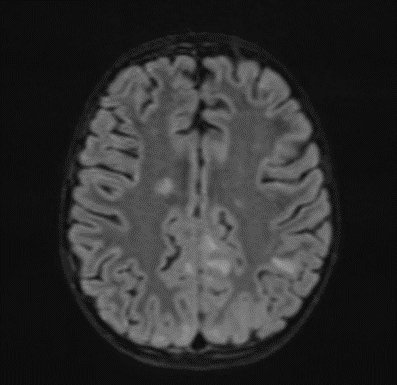

Subsequently, an MRI of the brain was performed, which demonstrated: Bilateral diffuse high signal changes in the cerebellum on T2 and FLAIR sequences, as well as areas of restricted diffusion, indicating focal zones of cytotoxic edema.

Picture 2.

The MRI of the brain revealed the following findings:

- Bilateral subcortical zones, predominantly in the occipital region, exhibiting confluent hyperintense signals on T2 and FLAIR sequences, accompanied by edema.

- A suspected area of cytotoxic edema in the superior parietal lobe.

- High signal intensities on T2 and FLAIR sequences observed in the centrum semiovale, right of the corpus callosum body, and bilaterally in the frontal gyrus, without diffusion restriction.

- In the supraventricular region, extending inferiorly from the projection of the postcentral gyrus into the subcortical white matter to the posterior part of the corpus callosum body (excluding it), and in the left superior temporal lobe, there was a cortico-subcortical lesion characterized by cytotoxic edema and restricted diffusion.

Picture 3.

The changes observed are characteristic radiological markers appreciated on DWI, indicative of cytotoxic edema. The DWI changes are considered reliable early signs of acute toxic encephalopathy, specifically methotrexate-related leukoencephalopathy. Post-contrast MR images did not show any abnormal contrast enhancement.

Bilateral Occipital Dominant Subcortical Hyperintense Zones: These areas were evident on T2-weighted and FLAIR sequences, indicating diffuse cerebral involvement. The predilection for the occipital region was consistent with reported cases of MTX-LE, which often presents with symmetric white matter changes.

Edema and Cytotoxic Edema: The superior parietal lobes showed suspected zones of cytotoxic edema. This was further supported by the presence of diffusion-weighted imaging (DWI) changes, characterized by restricted diffusion, a hallmark of cytotoxic edema. These findings align with the pathophysiology of MTX-LE, where MTX-induced neuronal damage leads to cellular swelling and subsequent restricted diffusion.

Supraventricular and Frontal Gyrus Involvement: High signal intensities on T2 and FLAIR sequences were noted in the centrum semiovale, right of the corpus callosum body, and bilaterally in the frontal gyrus, without diffusion restriction. This suggests early involvement before the development of significant cytotoxic damage.

Cortico-Subcortical Lesion in the Left Superior Temporal Lobe: This region exhibited cytotoxic edema with restricted diffusion, underscoring the multifocal nature of MTX-LE. The involvement of both cortical and subcortical areas is a typical feature in severe cases of MTX-LE.